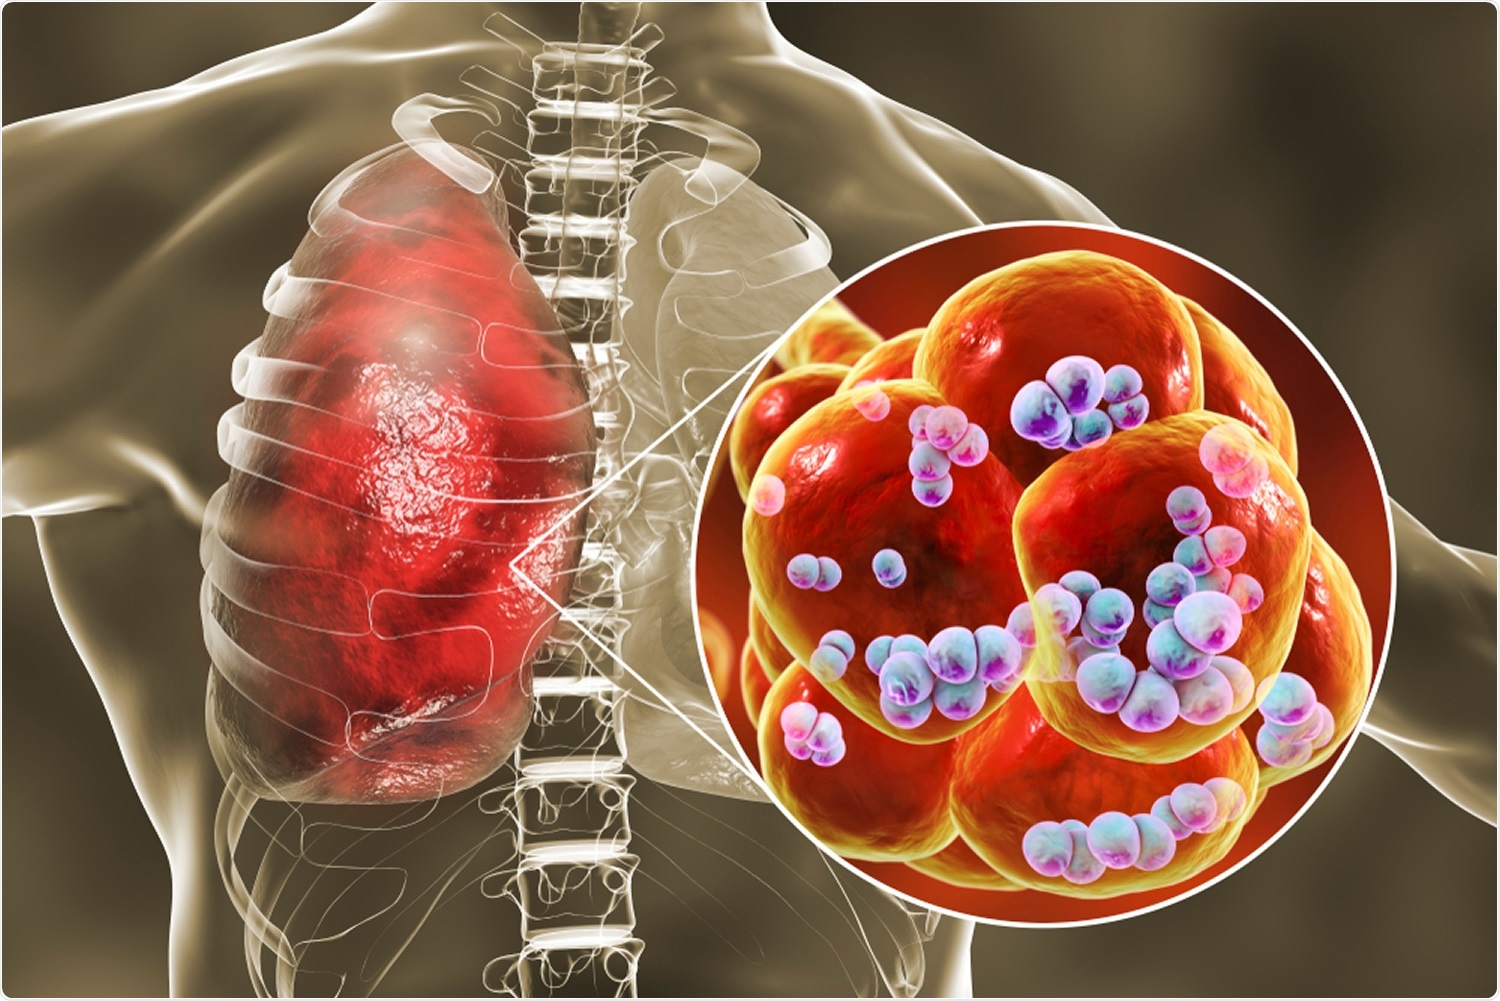

Фотографии бактерий, вызывающих бактериальные пневмонии у животных

Раздел: Другие животные